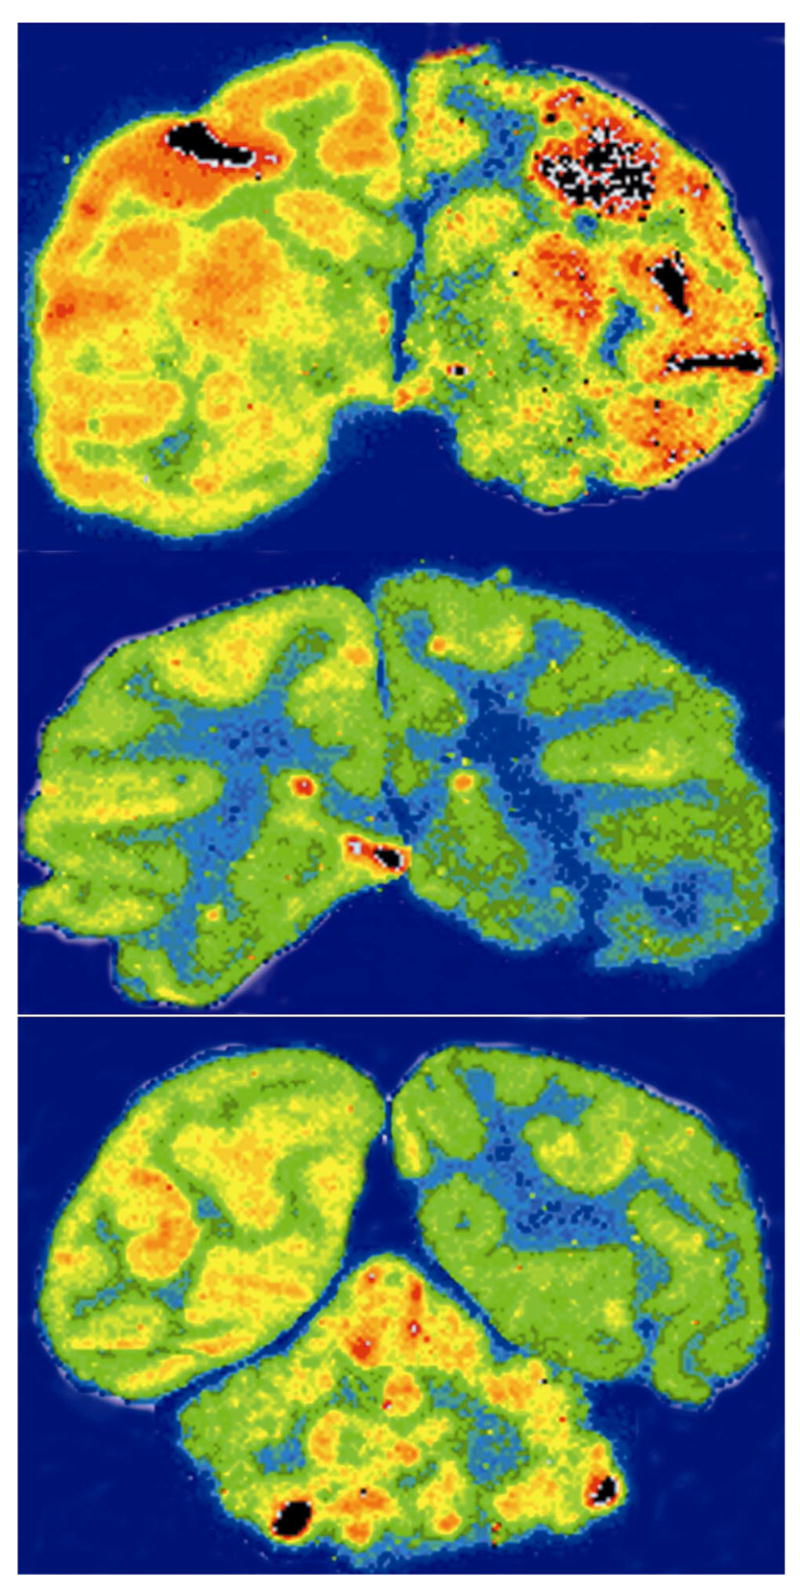

The fusion antibody was radiolabeled with 125-iodine, the hybridoma-derived mouse anti-Abeta MAb was tritiated, and the labeled antibodies were co-injected intravenously into an anesthetized adult female Rhesus monkey. In the first 3 hours after injection, there was no measurable decrease in the blood concentration of the [3H]-mouse Abeta MAb, whereas there was an immediate clearance of the [125I]-fusion antibody from blood in the primate (Figure 6a). The extensive distribution of the fusion antibody into the primate brain is shown by the 3 hour brain scan (Figure 7). There is global uptake of the fusion antibody in all parts of the brain with a preferential uptake in gray matter relative to white matter. Brain radioactivity at 3 hours after intravenous injection was measured with the capillary depletion technique, which demonstrated a high volume distribution (VD), >100 uL/g, of the [125I]-fusion antibody (Figure 6b). In contrast, the brain VD for the [3H]-mouse anti-Abeta MAb is 10 μl/g brain. This VD is equal to the arterial blood volume of brain (27), and indicates the mouse anti-Abeta MAb does not cross the BBB in the blood to brain direction. The VD of the fusion antibody was high in the postvascular supernatant, indicating the fusion antibody is transcytosed across the BBB into the postcapillary compartment of brain (Figure 6b).

Figure 7. Global distribution of fusion antibody to primate brain.

Brain scans of adult Rhesus monkey at 3 hours after the intravenous administration of the [125I]-fusion antibody demonstrates widespread distribution of the fusion antibody into the primate brain in vivo from blood. The top scan is the most frontal part of brain, and the bottom scan is the most caudal part of brain, and includes the cerebellum.

The purpose of this investigation was to genetically engineer an anti-Abeta antibody that can also cross the BBB in both the blood to brain and brain to blood directions. Therefore, an anti-Abeta ScFv antibody was fused to the heavy chain of the genetically engineered HIRMAb to enable receptor-mediated transport in the blood to brain direction across the BBB via transport on the endogenous insulin receptor. The HIRMAb is not recognized by the rodent insulin receptor, but is recognized by the insulin receptor of Old World primates such as Rhesus monkeys, but not New World primates such as squirrel monkeys (14). The selective transport of the fusion antibody across the primate BBB, relative to the murine anti-Abeta MAb is demonstrated in Figure 6b. There is no measurable clearance of the murine anti-Abeta MAb from primate blood at 3 hours after intravenous administration (Figure 6a), because this antibody, which is a mouse IgG1, does not recognize any receptor that would mediate selective exodus from the blood compartment. The human FcRn, and presumably the primate FcRn, does not recognize mouse IgG1 (24). However, the lack of recognition of the murine anti-Abeta MAb by the primate FcRn cannot explain the lack of influx of this MAb from blood to brain. The BBB FcRn is an asymmetric transporter, and mediates only the efflux of IgG from brain to blood, but not the influx of IgG from blood to brain (18). In contrast to the slow clearance of the murine anti-Abeta MAb from blood, the fusion antibody is rapidly removed from the blood (Figure 6a), owing to uptake via tissues such as liver, spleen, and brain that express vascular insulin receptor (14). This rapid removal of fusion antibody is likely mediated by the insulin receptor, since the rate of removal of the fusion antibody from the blood compartment of the Rhesus monkey is virtually identical to the rate of removal of the genetically engineered HIRMAb reported previously (15,16). The systemic clearance of the [111In]-chimeric HIRMAb, 0.22±0.08 ml/min/kg (15), is not significantly different from the systemic clearance of the [125I]-fusion antibody, 0.18±0.05 ml/min/kg. The 3-hour brain scan of the primate shows global distribution of the fusion antibody in the primate brain in vivo with a greater uptake in gray matter relative to white matter (Figure 7). This pattern of uptake reflects the approximate 3-fold greater vascular density in gray matter relative to white matter, and thus 3-fold greater density of microvascular insulin receptor in gray matter as compared to white matter (14). The rapid transport of fusion antibody across the primate BBB in vivo is confirmed by measurements of brain VD (Figure 6b). The brain VD of the murine anti-Abeta MAb, 10 μl/g (Figure 6b), is equal to the cerebral arterial blood volume (27), which indicates the murine anti-Abeta MAb does not cross the BBB in vivo in the blood to brain direction. In contrast, the brain VD for the fusion antibody is >100 μL/g brain (Figure 6b). Capillary depletion analysis shows that the fusion antibody undergoes transcytosis across the BBB and penetrates into the postvascular volume of brain (Figure 6b). Once inside brain, an anti-Abeta antibody may bind amyloid and cause disaggregation of the amyloid plaque.